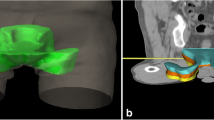

Three new clinical target volumes were defined and extended by 1 cm to create the PTVs. First, the original CTV was reduced by 1, 2 and 3 cm (longitudinal) and if necessary, adjusted to bones and vessels. By using 1 cm safety margin of these CTVs, PTVs were defined for each patient: The standard PTV minus 1 cm cranially (PTV-1), the standard PTV minus 2 cm cranially (PTV-2) and the standard PTV minus 3 cm cranially (PTV-3) (Fig. 1). The goal was to keep the shortest PTV (PTV-3) at least 2 cm above the last macroscopically visible primary tumor or lymph node metastases on MRI scan.

Change in dose distribution after a target volume reduction of 3 cm. Protection of OARs. Differences in dose distribution (colour-wash) of the original bPTV (left) and the cranial 3 cm reduced PTV (3 cm, right). Especially the low and middle dose range covering less volume of the peritoneal space (green shape) and the bladder (yellow shape)